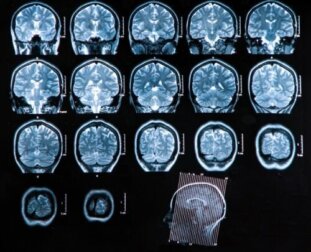

- Computertomographie: Sie ist von großem diagnostischen Nutzen, da sie es dem Arzt/der Ärztin ermöglicht, alle Zusammenhänge mit der Erkrankung zu überprüfen und die Behandlung entsprechend der jeweiligen Phase festzulegen. Diese Technik ist auch eine gute Untersuchung, um die Entwicklung der Pathologie nach der Behandlung zu verfolgen.

- Magnetresonanztomographie: Die Magnetresonanztomographie ist die beste bildgebende Untersuchung für die Diagnose eines Hirnabszesses. Sie ist viel empfindlicher als die Computertomografie und bietet viele Vorteile bei der Erkennung von frühen Hirnentzündungen und Ödemen. Außerdem ermöglicht sie eine bessere Unterscheidung zwischen Entzündungsherden und anderen betroffenen Strukturen.